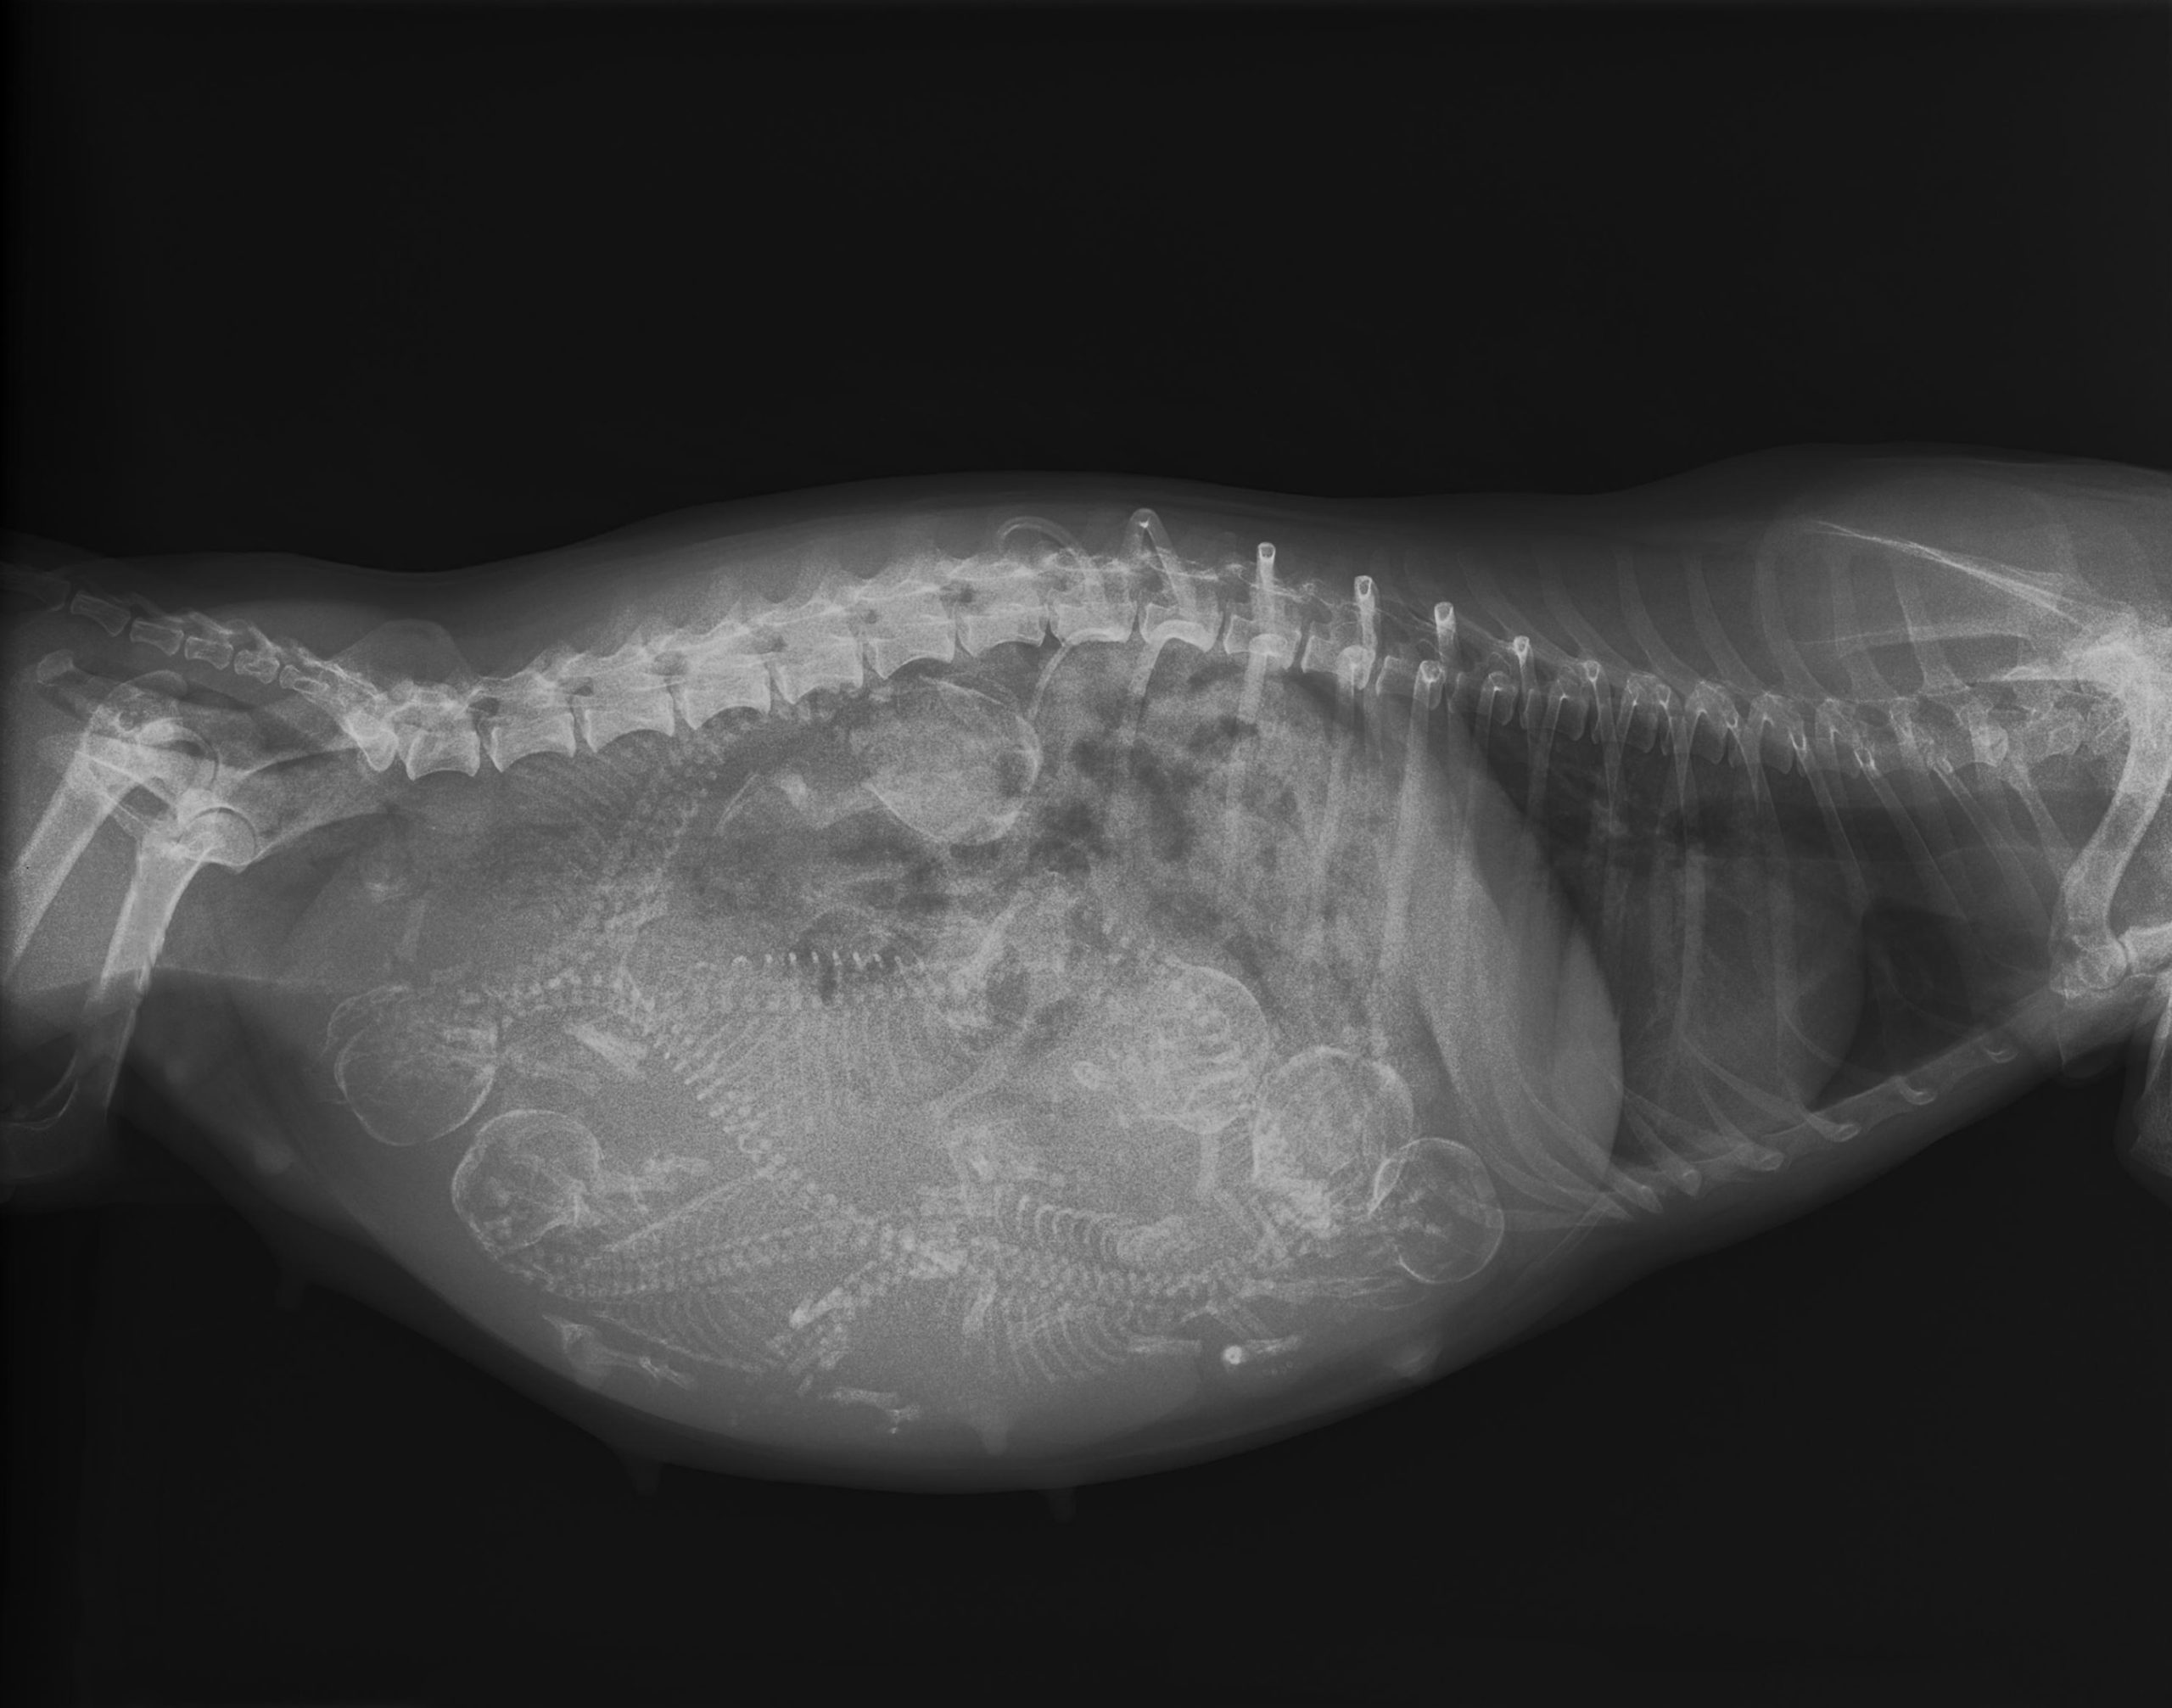

The one question vets hate hearing as they ultrasound expectant canine mothers is “how many puppies are there?” The reason is that, on ultrasound, this can be very difficult to accurately measure, particularly if the litter is a large one. It’s not uncommon for breeders to count their ‘chickens’ before they’ve hatched, and it can be quite awkward if they’ve already sold pups based on your ‘estimate’. While an X-ray can provide a more accurate number by allowing you to do a literal head count, exposing mother and babies to unnecessary radiation is not typically advised.

In the case of Marigold, the two-year-old Irish Setter from Canterbury, UK, not even an X-ray could have prepared her owner for the number of pups that made their appearance over the course of a cold January day.

Dubbed “Irish Doodles” as their Irish Setter mother was mated to a Poodle, it is believed that this is the largest litter of this particular crossbreed born in the UK. What’s even more astounding, however, is that it is still only two-thirds the size of the largest litter on record.

Of course, Marigold deserves particular recognition for having delivered all 17 puppies naturally. Whilst the relative size of pup to mother means that there is less physical exertion required to expel each pup compared with that of a human baby, spending almost 12 hours pushing, resting, cleaning, feeding, and pushing again is almost too exhausting to think about.